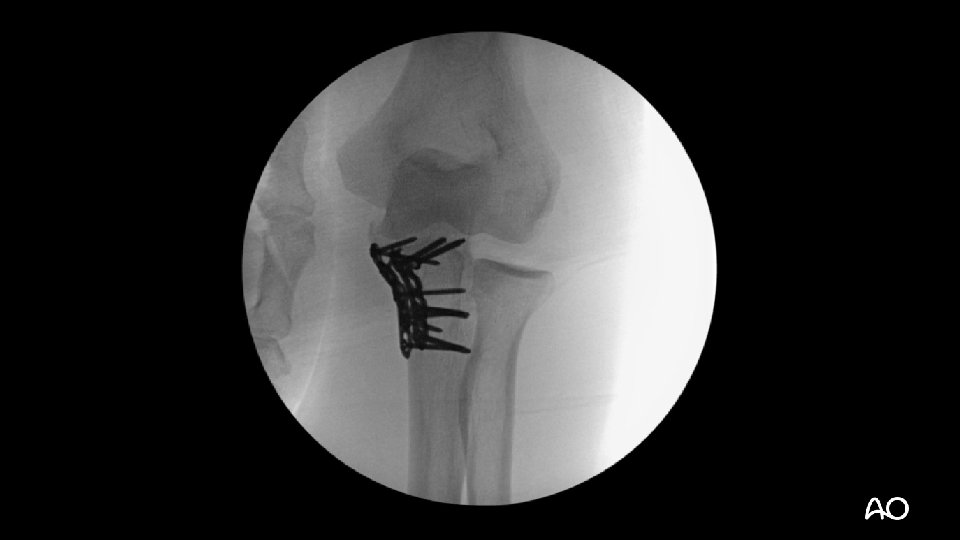

Transolecranon—tactic • Address coronoid fractures through olecranon fracture line • Anatomically reduce olecranon • Plate-and-screw constructs are often necessary (no tension band) • Normally, ligaments are relatively spared

Transolecranon—tactic • Extensile posterior exposure • Full-thickness cutaneous flaps: • Can access Kocher (ECUanconeus) interval for radial head repair/replacement if necessary